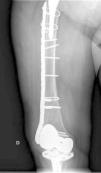

All the patients have been treated surgically with spinal anaesthesia with reduction and internal fixation with an angular-stable plate. Scheduled surgery was performed on average 2.5 days from occurrence of the fracture, overlapping the femoral stem of the hip implant between 3 and 10cm, placing 3 percutaneously and 4 by open surgery. The plate was stabilised with screws using accessory wires in the proximal segment depending on the fracture line. None of the hip or knee implants had been revised and no autologous or allografts had been used in any of the cases.

The interprosthetic fractures occurred between 2 and 8 months after the hip surgery, all of them were low-energy produced. In four cases they were located at diaphyseal level and in three at supracondylar level, two with ultracongruent and one with posterior stabilised polyethylene. In all cases both implants were stable and not affected by the fracture line. In two cases the fracture line affected the distal cement plug of the hip arthroplasty (Fig. 1). Following Platzer's classification, the fractures were 4 type IA, and 3 type IIA adjacent to the knee arthroplasties (Figs. 3 and 4). Four patients were assessed with a Singh index of 3 and 3 with an index of 4.

All of the patients walked with the aid of orthopaedic devices prior to the fracture, 3 with a walking frame and 4 with crutches. Union took place in all cases with a mean of 4.5 months,4–7 two of them had diaphyseal fractures with delayed union. There were no angles in union greater than 5°, no reoperations or complications or evolutionary complications presented, even in one patient with a short plate which only overlapped 3cm who made satisfactory progress (Fig. 2). All the patients regained their walking ability prior to the fracture except for one female patient who was lost to follow-up at 6 months, the fracture having healed. Clinically, the three patients with a supracondylar fracture lost a mean of 20° knee flexion, previous hip mobility was not altered in any of the patients.

We have followed the abovementioned criteria, using a single lateral angular-stable plate in all cases covering the entire interprosthetic femoral segment, achieving union in all cases with no reoperations or failures. The only problem that we found was achieving an adequate overlap of the osteosynthesis plate to the femoral hip implant, since the reduced availability of plate lengths means that occasionally we have to make a rather limited or excessive overlap; a choice has to be made between one or the other.